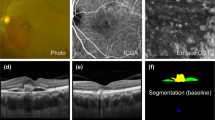

A custom deep learning algorithm based on the improved residual U-Net architecture was used to automatically segment the choroid boundaries of all images. This neural network model was trained based on OCT images of 382 emmetropic and 217 highly myopic eyes, with an accuracy rate of 95% for correctly identifying choroidal boundaries. The results of choroidal boundary segmentation were checked twice. For images with segmentation errors, manual corrections were applied. Additionally, due to the impact of parapapillary atrophy (PPA) on the accuracy of choroidal boundary segmentation, images with severe PPA underwent manual segmentation. ChT was determined by measuring the distance between the choroidal boundaries. Subsequently, the luminal area (LA) and stromal area (SA) within the choroid were precisely defined. This precision was achieved through the application of Niblack auto-local threshold algorithm on binarized OCT images. The choroidal vascular index (CVI) was calculated as the ratio of the LA to the total choroidal area (TCA, LA + SA). Choroidal parameters were assessed across ten specific regions as depicted in Fig. 1.

Illustration of choroidal image binarization and choroidal vascular parameters analysis. a The original swept-source optical coherence tomography (SS-OCT) image. b Segmentation of the choroidal boundaries. c Binarization of the choroidal area. d Overlay of the region after performing image binarization. e Vertical scan. f Horizontal scan. Regions: C, fovea; I1, inferior parafovea; I2, inferior perifovea; S1, superior parafovea; S2, superior perifovea; T1, temporal parafovea; T2, temporal perifovea; N1, nasal parafovea; N2, nasal perifovea. The choroidal thickness (ChT), luminal area (LA), stromal area (SA), and choroidal vascular index (CVI) in a 6-mm submacular region centered on the fovea were analyzed. Mean values of choroidal parameters at the vertical and horizontal meridians as well as in each region were respectively calculated. The low-reflection areas indicated by the red arrow are the vascular lumens while the high-reflection areas indicated by the white arrow are the extravascular stroma